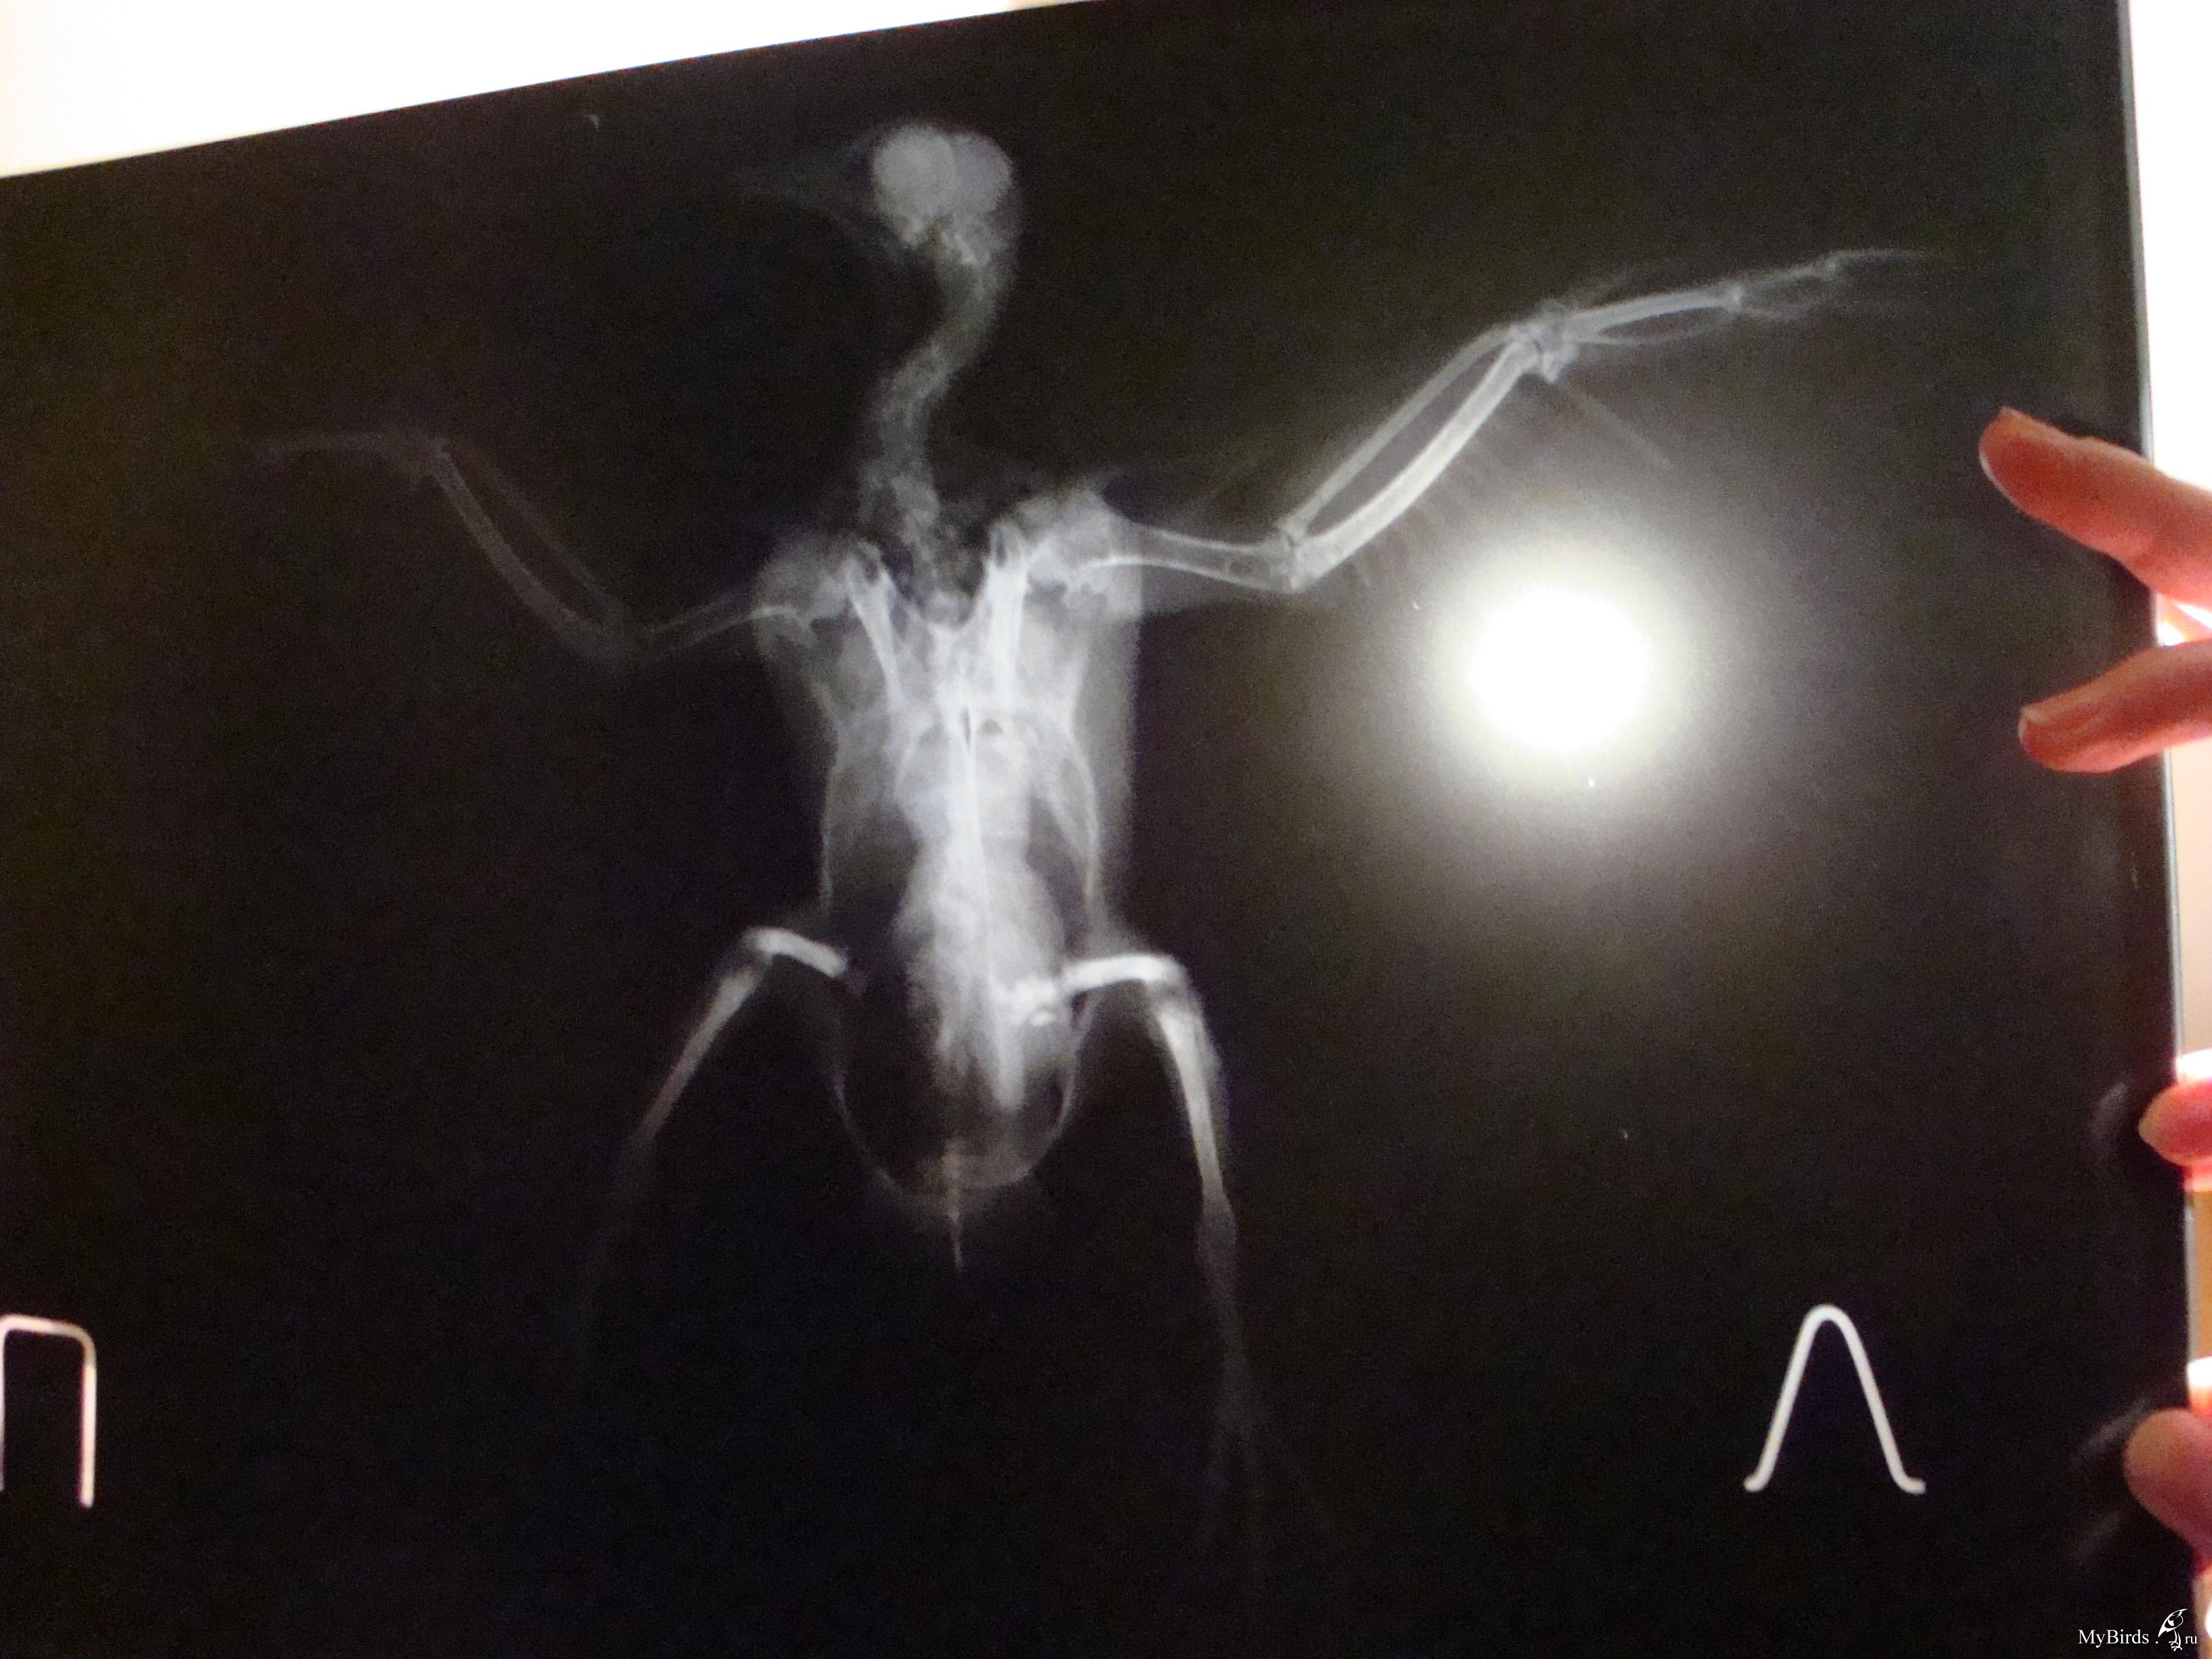

галина владимировна Опубликовано 11 сентября, 2009 Автор #118 Опубликовано 11 сентября, 2009 Это снимки Серого(тот,что с крылом).Хирург осмотрел крылья,проверил на рентгене и сказал,что перелома нет.У меня просьба.Пропишите пошагово ЧТО ДАВАТЬ,СКОЛЬКО И КАК ДОЛГО.Начиная с пробиотиков.И,если нужны витамины,то какие и тоже сколь.Схему лечения пропишите,пожалуйста,подробно(как для особо одаренных). Теперь Лапушка(тот,что с лапами).Для него такая же подробная нужна схема лечения.И чем протирать его гузку(попку).А то он лежит в своем помете часами. .Снимки,конечно ,оставляют желать лучшего.Но ,когда они были мокрыми,было видно хорошо.А высохли и изображение исчезло. У гули перелом обеих конечностей и перелом правого крыла.Хирург сказал,что крыло заживет само.А вот лапы..Переломы старые.Одна лапка сломана близко к суставу.Ее никто лечить не будет.А другую можно восстановить.Нужна операция. Операция стоит 6 тысяч.Помогите,пожалуйста, собрать средства!

Cheshirski Опубликовано 12 сентября, 2009 #120 Опубликовано 12 сентября, 2009 галина владимировна, поправил ваш пост с фотографиями - для удобства. Остальное - сейчас посмотрю-подумаю, и напишу. Снимки,конечно ,оставляют желать лучшего.Но ,когда они были мокрыми,было видно хорошо.А высохли и изображение исчезло.676983[/snapback] Маленький совет - просто вдруг в будущем пригодится. Снимки фотографировать лучше либо прямо на негаскопе (приспособление с подсветкой у врача в кабинете), либо на чем-то подобном дома (вроде светильника с лампами дневного света и молочным стеклом), а на худой конец - просто на окне, приклеив к стеклу скотчемза уголки, днем на фоне неба.Но ничего, и так все достаточно видно. Серенький. Да, переломов нет. Не видно и артроза - последствия сальмонеллы, к примеру - суставчики чистые (просто есть возможность сравнить - у меня есть снимок моего сальмонеллезника с артрозом). Тогда подвисание крыла - следствие ушиба или небольшого растяжения - они на снимке могут быть и не видны (сильные - видны в виде затемнения - притока крови к пострадавшему месту).Он не истощен? Пока кормите и добавьте в воду Ветом 1.1 - он есть? А в клюв ампульный препарат траумель, по такой схеме:Первый день приема - 2 капли в клюв каждые час.Второй день - 2 капли в клюв каждые 2 часаТретий день - 2 капли каждые 3 часа, и далее даете так, чтобы в день было не менее 3-4 приемов. Можно еще и крыло мазать траумелем (мазь), но если перьев много - то не стоит - оперение замаслится.И посмотрим за состоянием. Лапушка. Перелом крыла - да, такой сам срастется, если крыльями очень махать не будет. Смещение есть, но небольшое, на локтевой кости около запястного сустава. Даже летать сможет, скорее всего. И не исключено, что прилично летать.Лапы.Правая - да, трудный перелом. Думаю, стоит все же зафиксировать его, примерно вот так:Здесь черным обозначены кости, красным - место перелома, синим - плотный материал, вроде плотного картона, вырезан по месту, его два куска - с обоих сторон лапы - снаружи и изнутри, между лапой и телом. Конечно, подсогнуть надо будет, чтоб лапку облегал. А зеленым - места фиксации этой шины лейкопластырем. Другой вариант - выгнуть нечто подобное из жесткой (стальной) проволоки, и тоже закрепить на лапе пластырем. Возможно, что-то и удастся сделать, чтоб лапа более или менее правильно срослась. Левая. Тут попроще, кость сломана почти в середине. Что за операцйия предполагается? Остеосинтез - то есть, установка спицы? Попробуйте с врачом поговорить - не удастся ли просто совместить перелом и тоже наложить шину? Дело в том, что остеосинтез не всегда успешен у птиц - от многого зависит, и в любом случае, надо будет обеспечить неподвижность лапы, а со спицей это не всегда удается. Хотя, если у врача есть уверенность в результате - то можно попробовать. Про помет и т.д. При таких травмах не исключен и ушиб внутренних органов - той же печени. Плюс голодовка.Давайте ей траумель так же, как и Серенькому, и Ветом в воду тоже - по четверти чайной ложки на 100 мл поилки. Плюс карсил - по полтаблетки раз в день - это для печени, растолочь и давать в клюв разведенный водой до состояния кашицы.На кандиду картина не похожа, в крайнем случае - на нечто бактериальное. Пока не давайте, но имейте под рукой ципрофлоксацин 250 мг таблетки, наверняка еще остались. Если вдруг состояние кого-то из гуль будет хоть немного ухудшаться - давайте ципрофлоксацин в следующем разведении:1/2 таблетки развести в 4 мл воды, давать по 0,2 мл 2 раза в день в клюв. Если начнете его, то не прерывайте курс, давайте 10 дней. Если все же сделают остеосинтез - тогда надо будет поколоть другое лекарство, да и еще кое-что добавить, тогда и напишу. По поводу финансов - киньте в личку полный адрес, переводом сколько-то переправлю. ПС. В форуме, как правило, бываю каждый день. Так что не пропущу, единственно - не всегда удается отвечать оперативно.